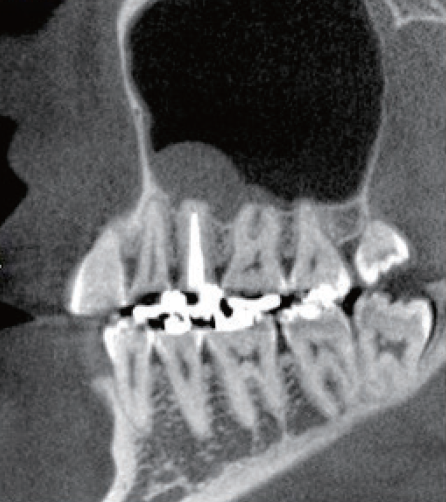

根管充填後のレントゲン所見を示す(症例1・③)。術前と比較し、レントゲン上では上顎洞粘膜の肥厚も改善傾向が認められる。根尖病変の主原因がバイオフィルムであり、機械的な拡大形成は必須であるため根管を3次元的に捉えて処置することが重要である。デンタルX線では近遠心的な形態は確認することができるが、頬舌的な形態を確認することは偏心投影をしても難しい。CBCTは根管処置を行う上で非常に有益な情報を得ることができると考える(症例1・④、⑤)。

(症例1・③)

根管充填、支台築造後のレントゲン像術前と比較しレントゲン上では上顎洞粘膜の肥厚も改善傾向が認められる

(症例1・④)

術前と比較して頬口蓋方向に膨らんでいた髄角部の形態の変化が確認でき、未処置部分が減少していることが確認できる。上顎洞粘膜の肥厚も術前と比較し改善傾向にある

(症例1・⑤)根尖部のCBCT像

根尖部の開口部は3つ以上存在し、根管充填材が開口部を封鎖していることが確認できる